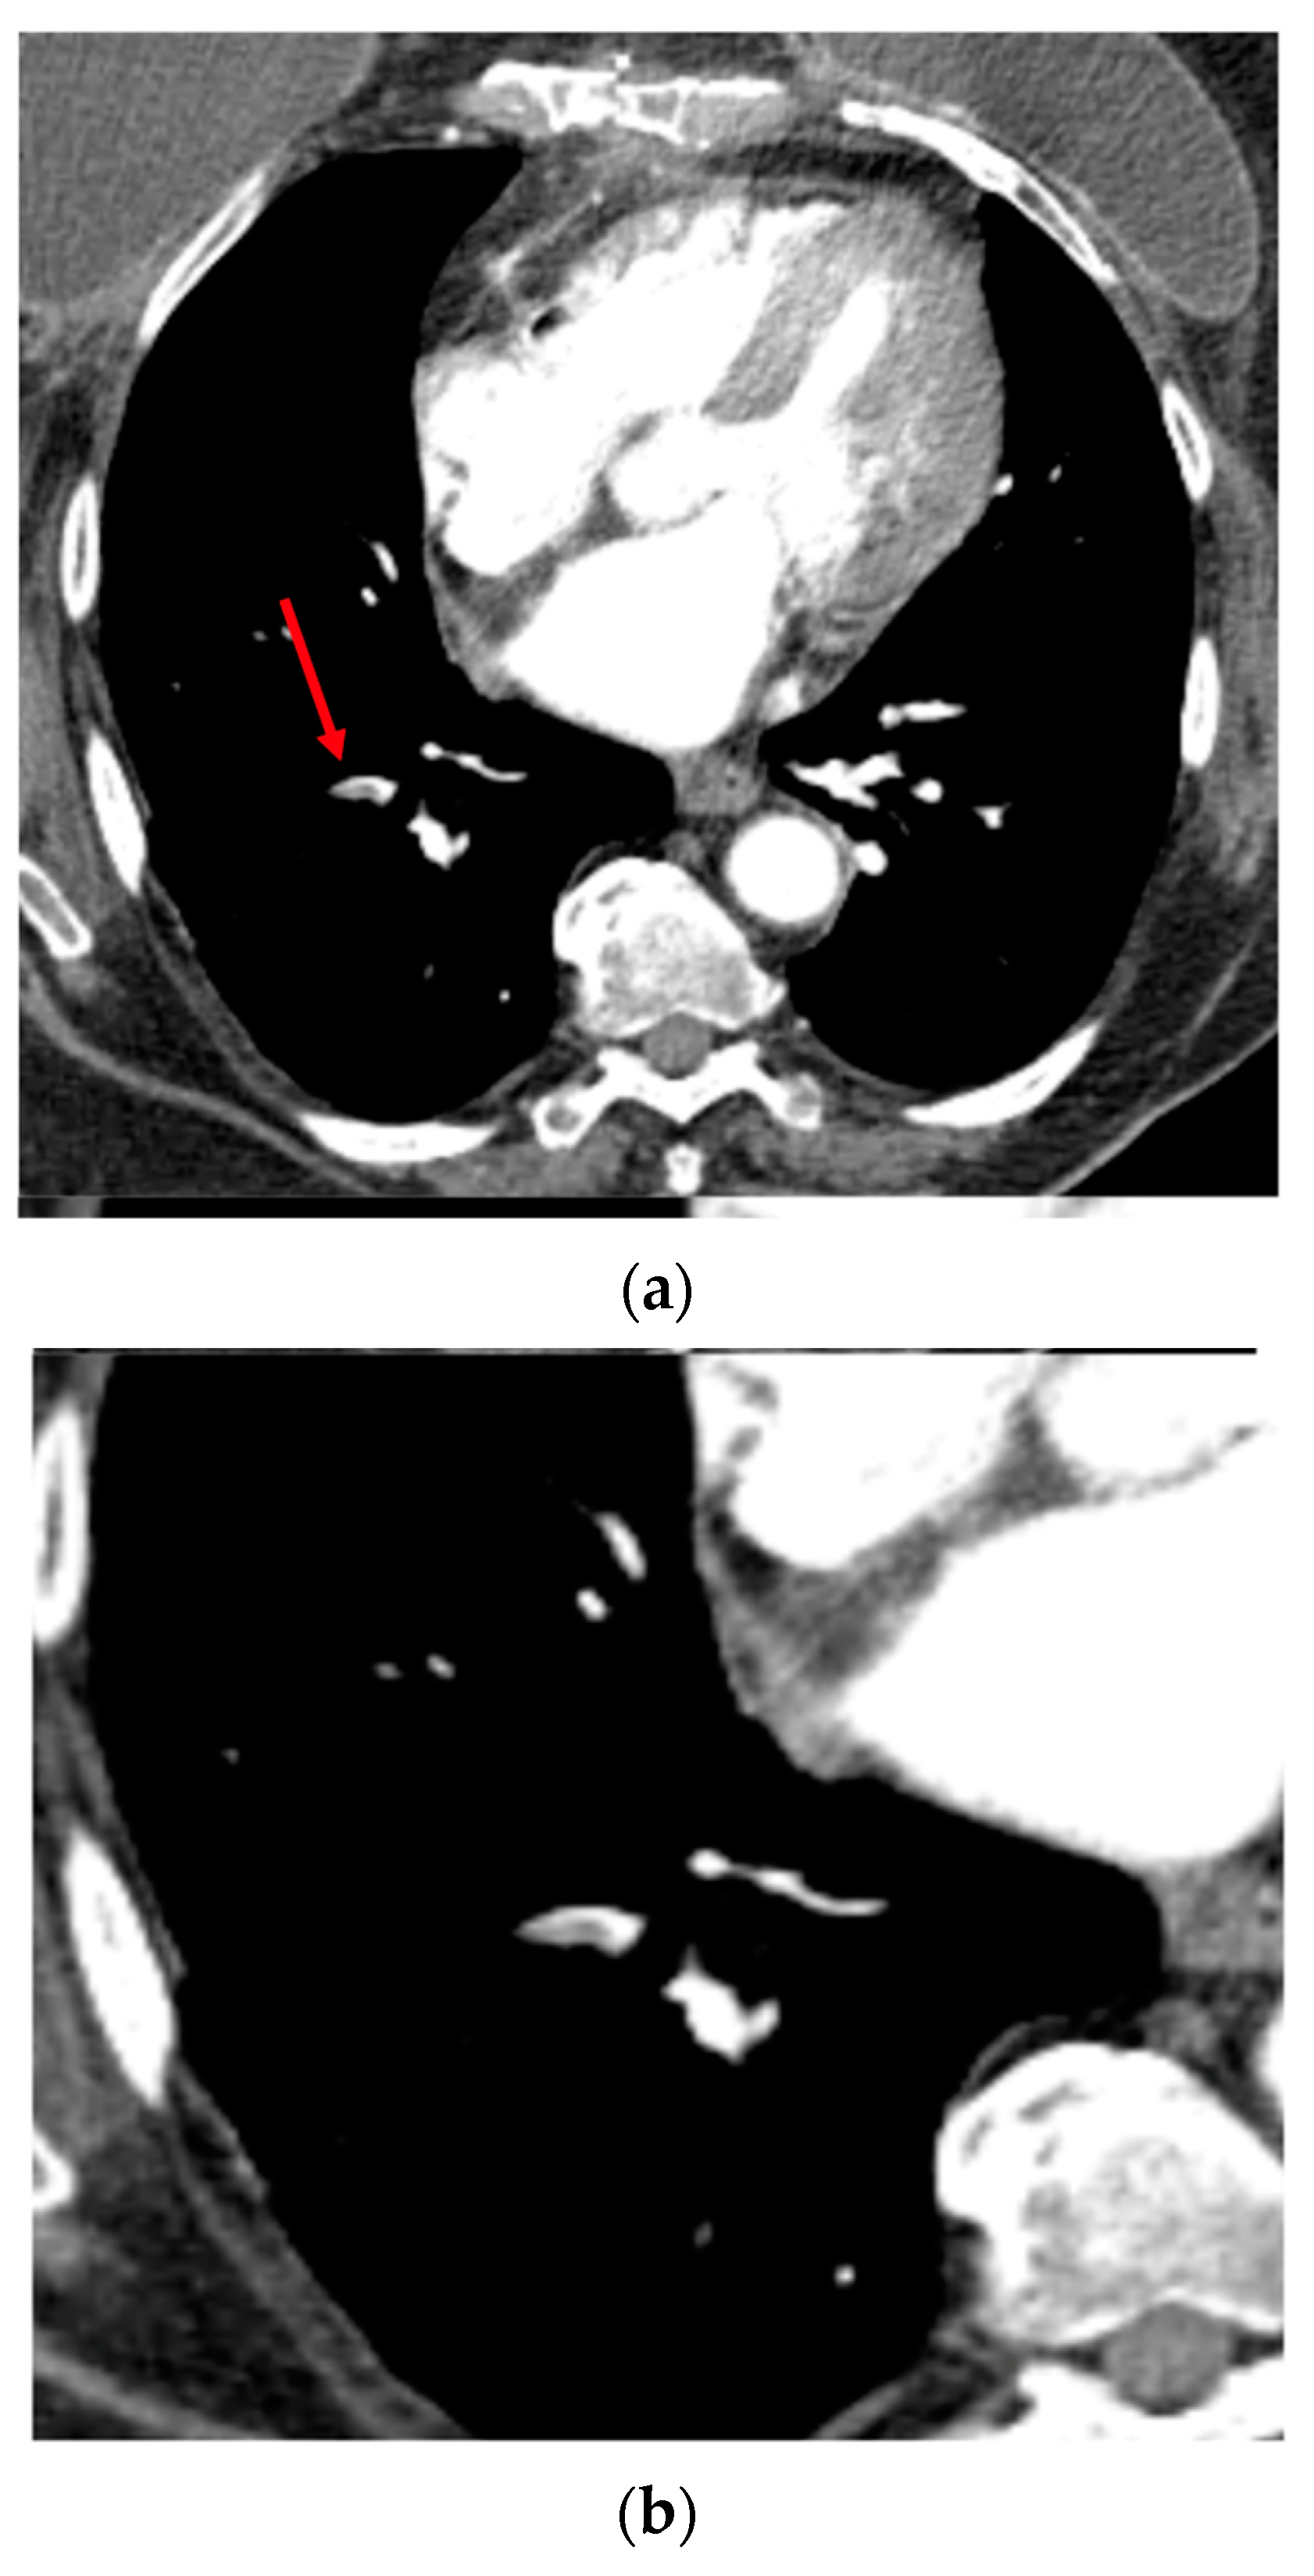

Figure 2.

Axial CTA image. Example of segmental pulmonary embolus (PE) in the right lower lobe (filling defect within the arterial lumen), correctly detected by the CINA-PE software considered as a true positive case. Top (a): The red arrow shows the clot within the arterial lumen. Bottom (b): Axial image targeted on the right lower lobe.